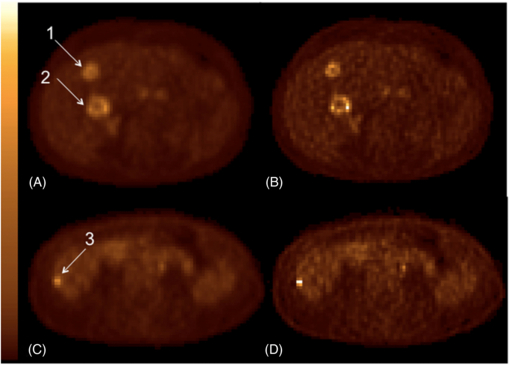

This example is for illustration purposes only. A phantom simulation study was performed in order to compare some of the PVC methods described above. A 2D synthetic phantom was used, consisting of a hot annulus and a cold centre. This could represent a brain study with GM (annulus) and WM (centre), or a cardiac study with myocardium (annulus) and ventricle (centre), or an oncological study with viable tumour (annulus) and necrosis (centre). The central region was uniform with a relative activity concentration value of 1, and the annular region was divided into various sections. On the left hand side, the main part of the annulus had a value of 4, except for a 30° cold-spot with a value of 2. The right hand side was divided into three 60° segments with values of 3, 4 and 8, respectively. Normally distributed random noise was added to the phantom which was then convolved with a PSF with a FWHM corresponding to 80% of the width of the annulus. PVC was performed as described above, using the MGM, GTM and RBV methods.

Figure 5 shows the true distribution in the phantom, the regional masks (or templates) used in the different methods, as well as the uncorrected and PV corrected images, using MGM and RBV. The MGM regional mask consisted only of the background (centre) and target (annulus) regions, while the RBV and GTM mask contained all the original regions except for the left-hand side cold-spot, which was treated as unknown. The difference between the masks is due to the fact that, although multiple background regions can be used with MGM, there can only be one target region in which the correction is applied. On the other hand, RBV and GTM can use any number of regions, and the correction is applied to all regions.

Figure 5. Top row: original phantom and regional masks (templates) used for MGM and RBV. Bottom row: the uncorrected simulated image with added noise and resolution blurring, and results after PVC with MGM and RBV.

Download figure:

Standard imageIt is clear from the images that the contrast in the annulus as well as the sharpness of the boundaries increases after PVC with both MGM and RBV. The difference between the two methods is that, while MGM does not perform any correction within the annular target region, RBV does correct for cross talk between different regions within the annulus. Also, the RBV corrected image retains information about the distribution in the central region, whereas in the MGM corrected image this region is just represented by a constant value. The left-hand side cold-spot is clearly visible in both PV corrected images.